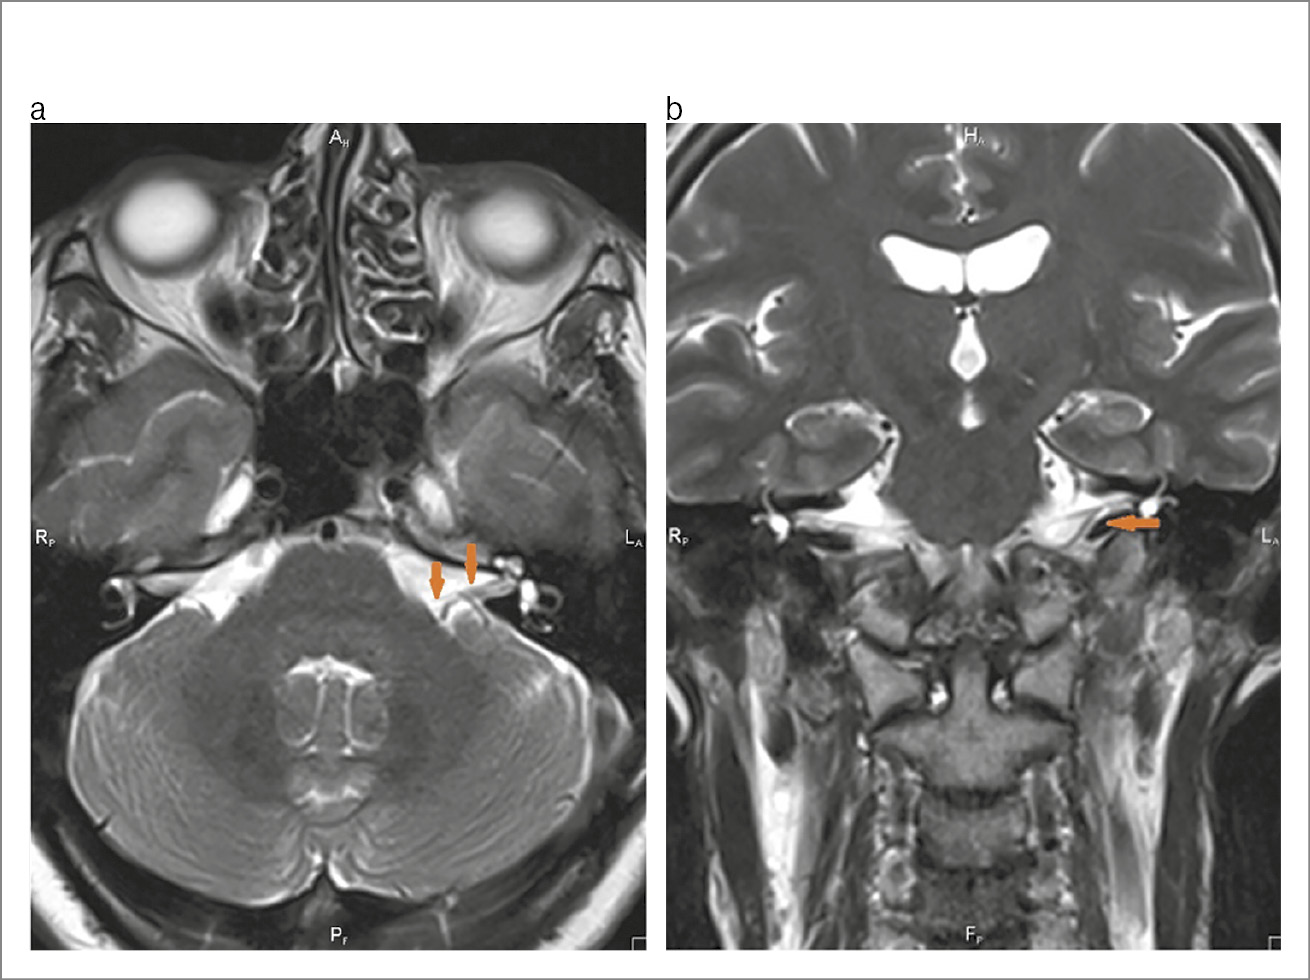

Лабораторно-инструментальные методы исследования: в клиническом и биохимическом анализах крови, общем анализе мочи отклонений от нормы не отмечено. По данным компьютерной томографии (КТ) височных костей патологических изменений в височных костях не выявлено (рис. 1). По данным КТ органов грудной клетки без патологических изменений очагового и/или инфильтративного характера в легких, верифицирован локальный участок пневмофиброза в верхней доле левого легкого; КТ-0. По результатам магнитно-резонансной томографии (МРТ) головного мозга обнаружены магнитно-резонансные признаки множественных очагов в белом веществе головного мозга (вероятнее всего, сосудистого характера), умеренного расширения субарахноидального пространства, низкое расположение миндалин мозжечка. Изменений в области мосто-мозжечкового угла не обнаружено (рис. 2, а, b). На магнитно-резонансной томографии черепных нервов с двух сторон визуализируется нормальный ход лицевых нервов (рис. 3). По данным ЭНМГ, выполненной на 5-е сутки от начала заболевания, определены признаки умеренно-выраженного поражения лицевого нерва слева. Характер поражения смешанный (поражение миелиновых оболочек и осевых цилиндров). Произвольная активация m. orbicularis oculi, m. orbicularis oris слева значительно снижена (рис. 4, а). Пациентка осмотрена оториноларингологом – данных за острую лор-патологию не выявлено, офтальмологом – OU «гипертоническая ангиопатия сетчатки».

Рис. 1. Лицевой нерв в лабиринтной части фаллопиева канала на КТ височных костей.

Рис. 2, а, b. Лицевой нерв на МРТ головного мозга.

Рис. 3. Лицевой нерв на МРТ черепных нервов: а – правый лицевой нерв; b – левый лицевой нерв.